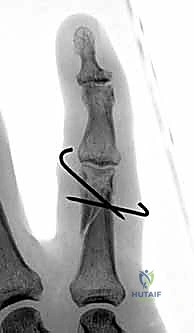

- تشوه مرئي في الإصبع: قد يبدو الإصبع أقصر من الطبيعي، أو منحنياً بزاوية غير طبيعية، أو ملتفاً حول محوره (Malrotation).

- ظاهرة تداخل الأصابع (Scissoring): وهي من أهم العلامات السريرية التي يبحث عنها د. هطيف. عند محاولة المريض إغلاق يده (صنع قبضة)، يتقاطع الإصبع المكسور فوق أو تحت الإصبع المجاور بدلاً من أن يشير بشكل متوازي نحو العظم الزورقي في المعصم. هذا يدل على وجود تشوه دوراني يجب تصحيحه جراحياً.